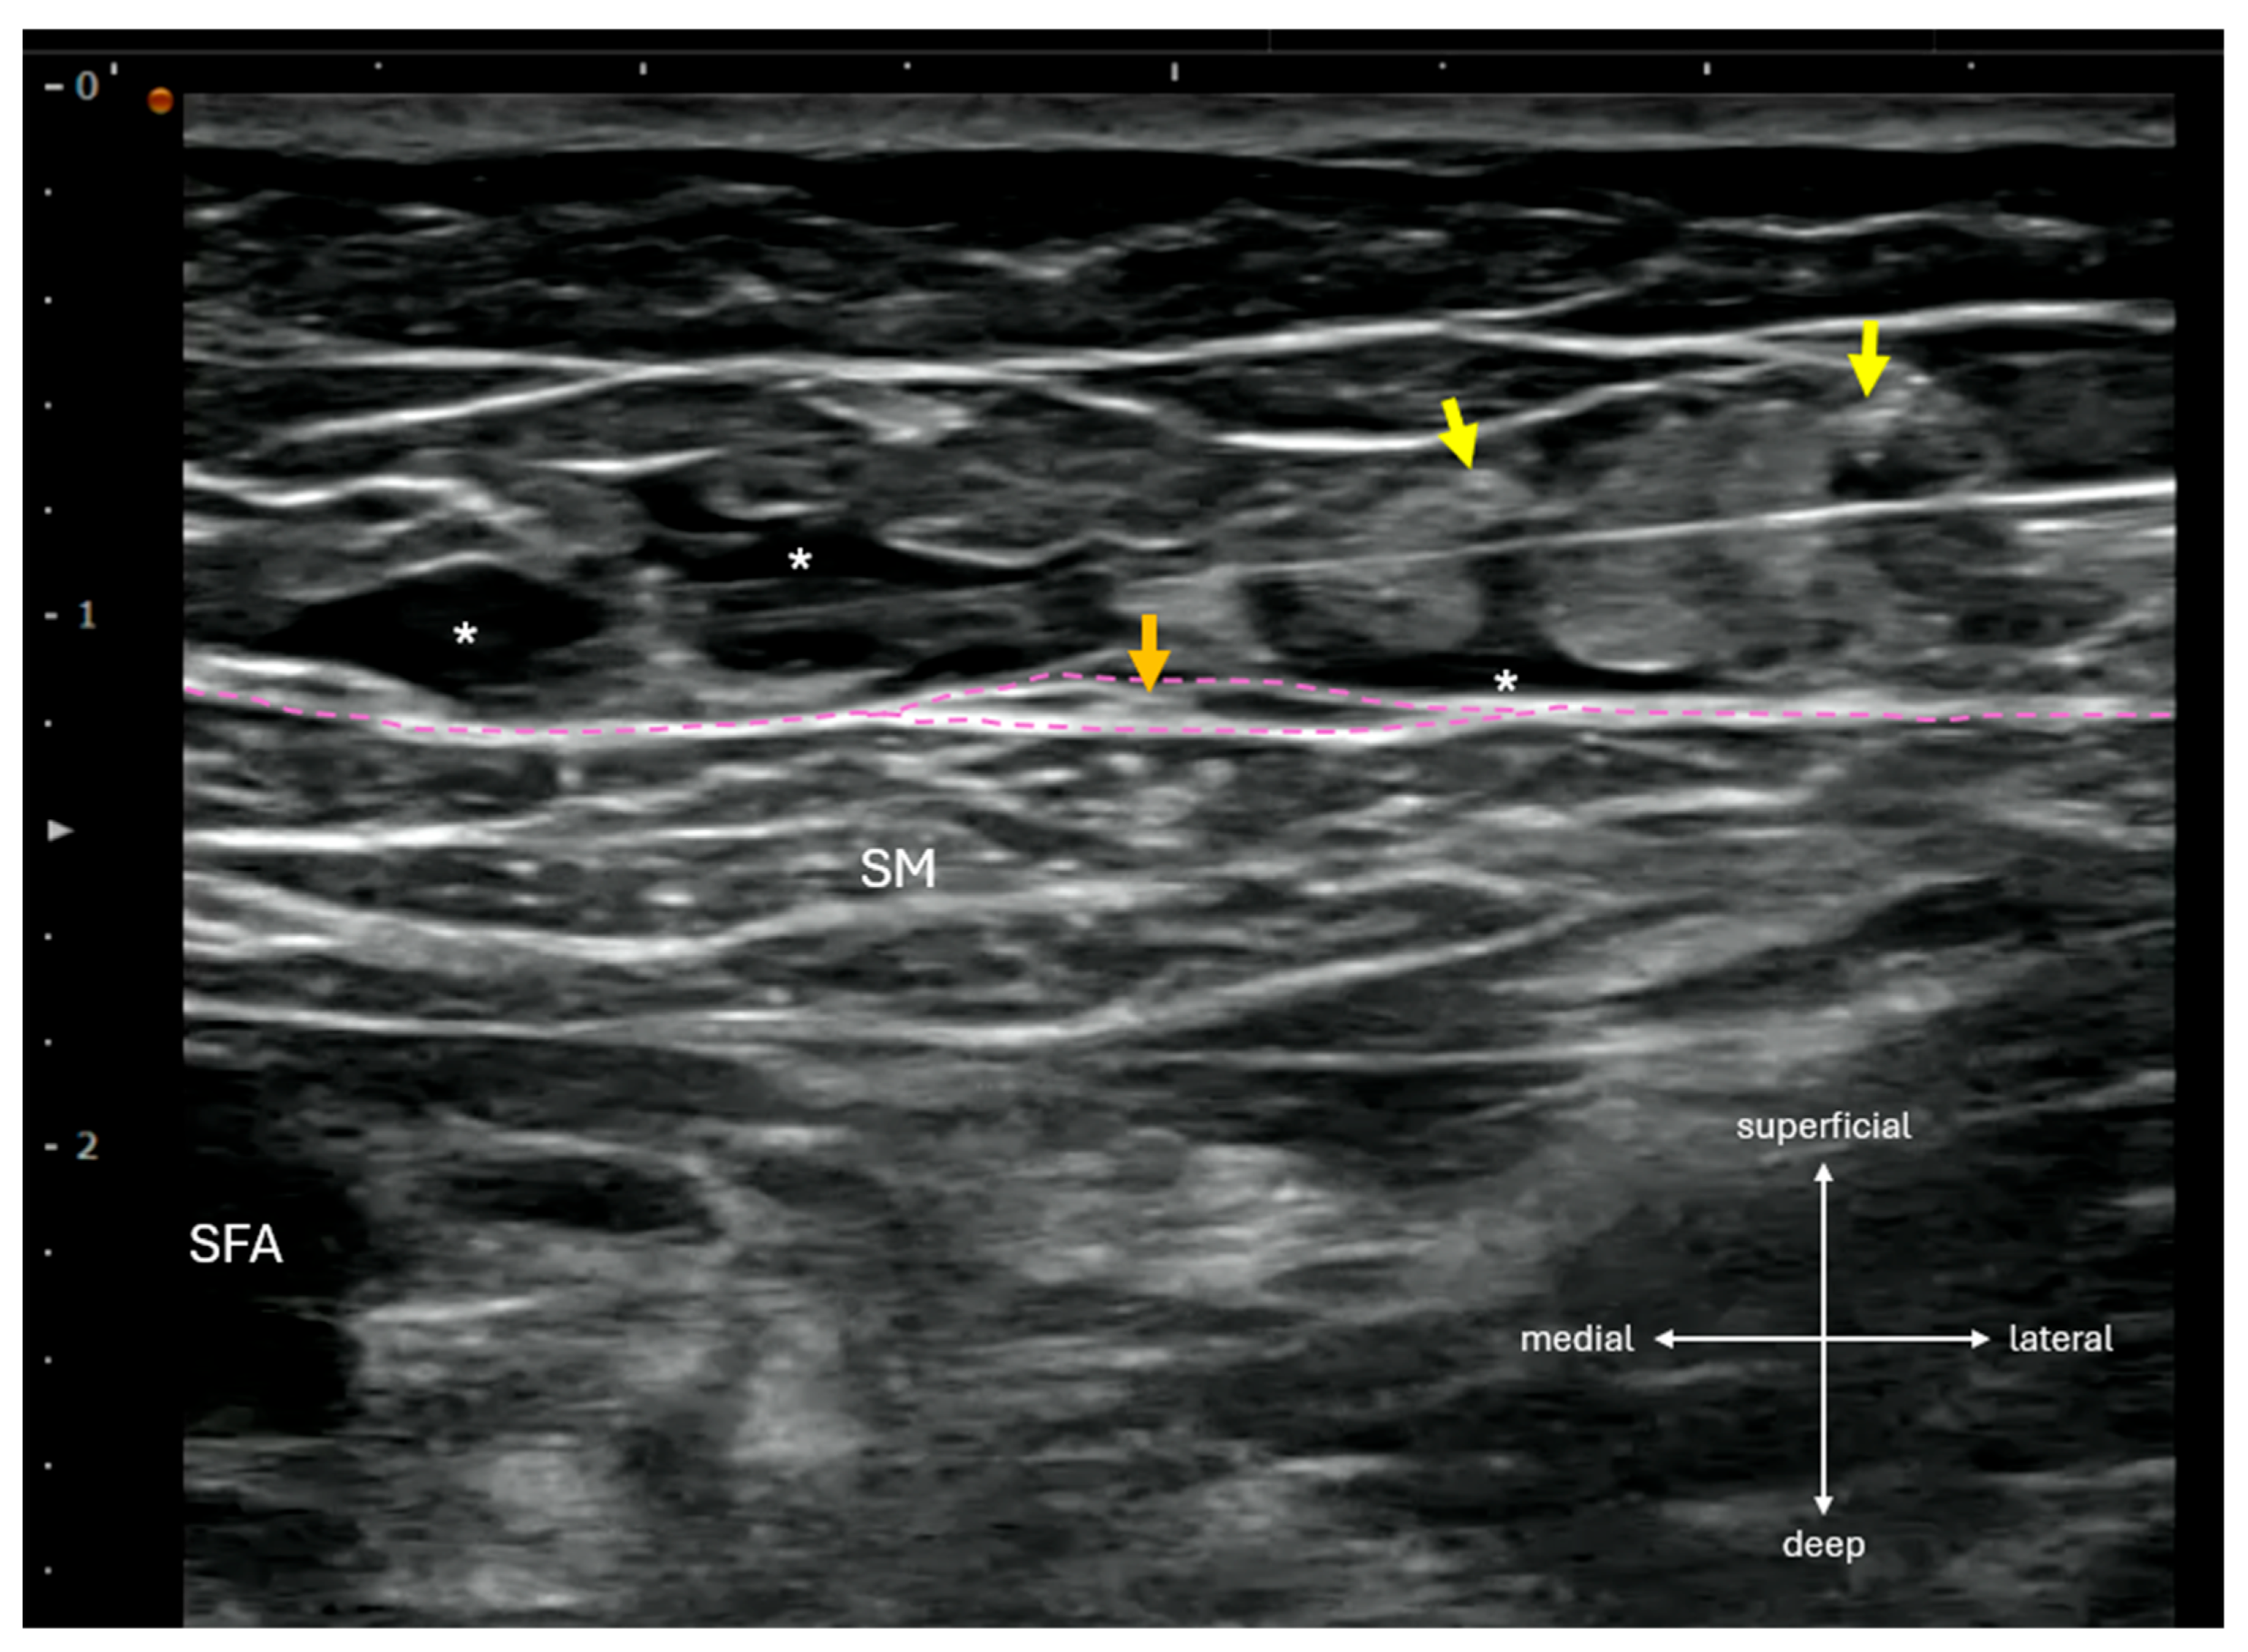

In the post-anesthesia care unit, SSSI was performed by infiltrating 20 mL of 0.3% ropivacaine from lateral to medial across the sartorius muscle at the femoral triangle apex, located sonographically at the intersection of the medial border of sartorius muscle and the medial border of adductor longus muscle. Using an inject-as-you-advance technique, local anesthetic was deposited evenly within the subcutaneous layer superficial to the fascia lata, while care was taken to avoid direct injection into hyperechoic structures resembling cutaneous nerves (Figure 1).

Figure 1.

Supra-sartorial subcutaneous infiltration (SSSI) performed in a lateral-to-medial direction at the femoral triangle apex, corresponding to the level commonly used for adductor canal block (ACB) or distal femoral triangle block. On ultrasound, anterior femoral cutaneous nerve (AFCN) branches appear as small, hyperechoic, ovoid structures superficial to the sartorius muscle (SM). The intermediate femoral cutaneous nerve (IFCN, yellow arrows) typically presents as two main branches in the subcutaneous layer, while the anterior branch of the medial femoral cutaneous nerve (MFCN-A, orange arrow) may be encased within a fascia lata duplicature (magenta lines). The course and branching pattern of these nerves, particularly the MFCN-A, are highly variable and often difficult to identify sonographically. *: local anesthetic; SFA: superficial femoral artery.